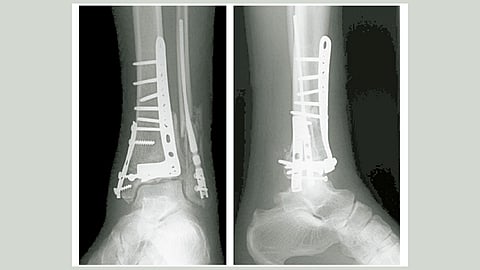

अपघातात हाडाला इजा पोहोचणे म्हणजे आयुष्यभर पुरणारी दुखापत. तुटलेल्या हाडांची झीज भरून निघावी आणि त्यांच्यातील जोड टिकावा यासाठी शस्त्रक्रियेद्वारे हाडांना धातूच्या सळईचा किंवा जाळीचा आधार देण्यात येतो. कालांतराने हाडे एकसंध झाल्यानंतर त्यांच्यामधून धातूची सळई बाहेर काढावी लागते. त्यासाठी पुन्हा एकदा शस्त्रक्रियेचा घाट डॉक्टरांना घालावा लागतो. सळई किंवा धातूची जाळी कायमस्वरूपी शरीरातच ठेवायची असेल, तर त्यासाठी विशेष काळजी घ्यावी लागते. जंतूसंसर्ग, फिजिओथेरपी, औषधे आणि शरीराच्या प्रतिक्रियांचा सामना वेळोवेळी रुग्णाला करावा लागतो. तुटलेल्या हाडांचे हे दुखणे कायमस्वरूपी बरे करण्यासाठी भारतीय शास्त्रज्ञांनी एक तोडगा काढला आहे. तेही आपल्या शरीरातील महत्त्वपूर्ण खनिज असलेल्या मॅग्नेशियमपासून विकसित केलेल्या मिश्र धातूपासून !

मानवी शरीरातील हात, पाय, मांडी आणि पाठीच्या हाडांची लांबी एक फुटांपेक्षा जास्त असते. पाच सेंटिमीटरपेक्षा जास्त लांबीचे फ्रॅक्चर भरून काढण्यासाठी वेळेबरोबरच आधाराचीही गरज असते. जोडलेल्या हाडांची हालचाल होऊ नये, त्यांना आधार मिळावा म्हणून टिटॅनियमपासून बनलेली जाळी वापरण्यात येते. परंतु, शरीरात जास्त काळ राहूनही तिचे विघटन होत नाही. पर्यायाने स्नायूंच्या पेशी आणि जाळीमध्ये तणावाची स्थिती निर्माण होते. शास्त्रज्ञांनी मॅग्नेशियमच्या नॅनोपार्टिकलबरोबर पॉलिकॅप्रोलेक्टॉन आणि हायड्रॉक्सिपीटाईटचे मिश्रण वापरून तयार केलेला हा नवीन पदार्थ हाडांच्या आधारासाठी शाश्वत उपाय आहे. ‘एझेड३१’ नावाच्या या मिश्र धातूपासून तयार केलेली जाळी लवचिक तर आहेच, पण त्याचबरोबर काही कालावधीने तिचे विघटनही होते. तसेच, त्यापासून कोणतेही विषारी रसायन तयार होत नसल्याने शरीरावरही कोणता विपरीत परिणाम होत नाही. ‘एझेड३१’ या मिश्र धातूची चाचणी करण्यासाठी शास्त्रज्ञांनी उंदराच्या हाडांमध्ये फ्रॅक्चर केले होते. त्यानंतर उपचारासाठी मॅग्नेशियमचे नॅनोपार्टिकल वापरलेली ही जाळी वापरण्यात आली. जाळीमुळे हाडांना आधार तर मिळालाच, पण त्याचा कोणताही दुष्परिणाम उंदराच्या शरीरावर जाणवला नाही. हाडे जुळण्यासाठी आवश्यक कालावधीपर्यंत ती जाळी टिकून होती. त्यानंतर काही कालावधीने जाळीचे विघटन होण्यास सुरुवात झाली. त्यामुळे तुटलेली हाडे भरून निघण्यासही मदत झाली. प्रयोगशाळेत उंदरांवर झालेले हे संशोधन हाडांच्या पुनर्बांधणीसाठी निश्चितच उपयुक्त ठरणार आहे. आता टप्याटप्याने इतर प्राण्यांवर आणि नंतर माणसांवर प्रत्यक्ष चाचणी झाल्यानंतर हे संशोधन सर्वसामान्यांच्या थेट उपयोगात येईल. भारतीय शास्त्रज्ञांचे हे संशोधन जगभरातील मानवजातीच्या कल्याणासाठी उपयोगी पडणार आहे.